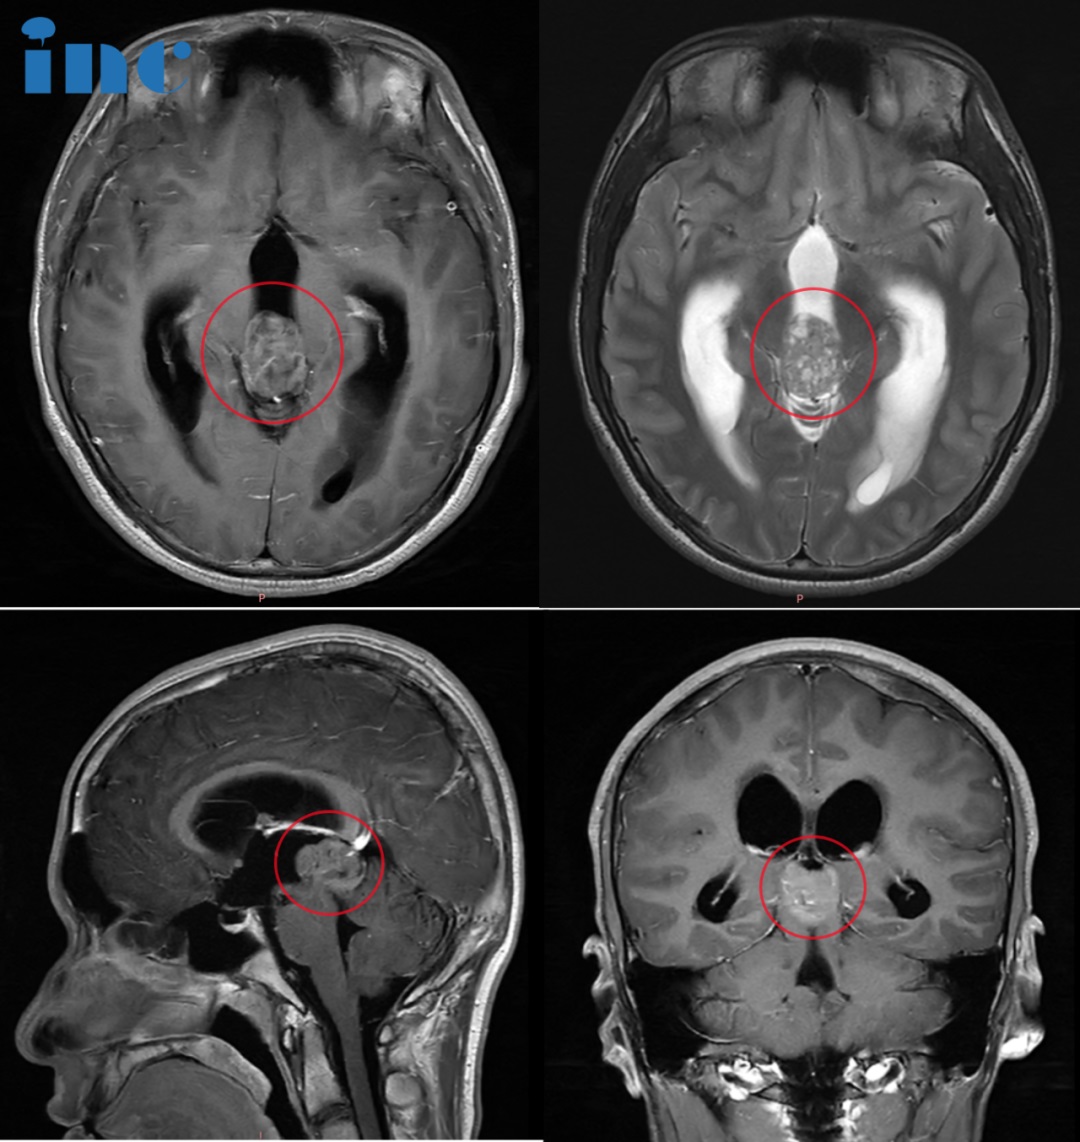

影像特征

矢状位及横断位T1WI+C示松果体区明显强化肿块,鞍上也可见小的强化肿块;横断位T2WI+FLAIR示松果体区高信号肿块伴周围水肿。

横断位T1WI示松果体区高信号肿块,T2WI呈高信号,T21WI+FLAIR呈高信号,T1WI+C示部分强化